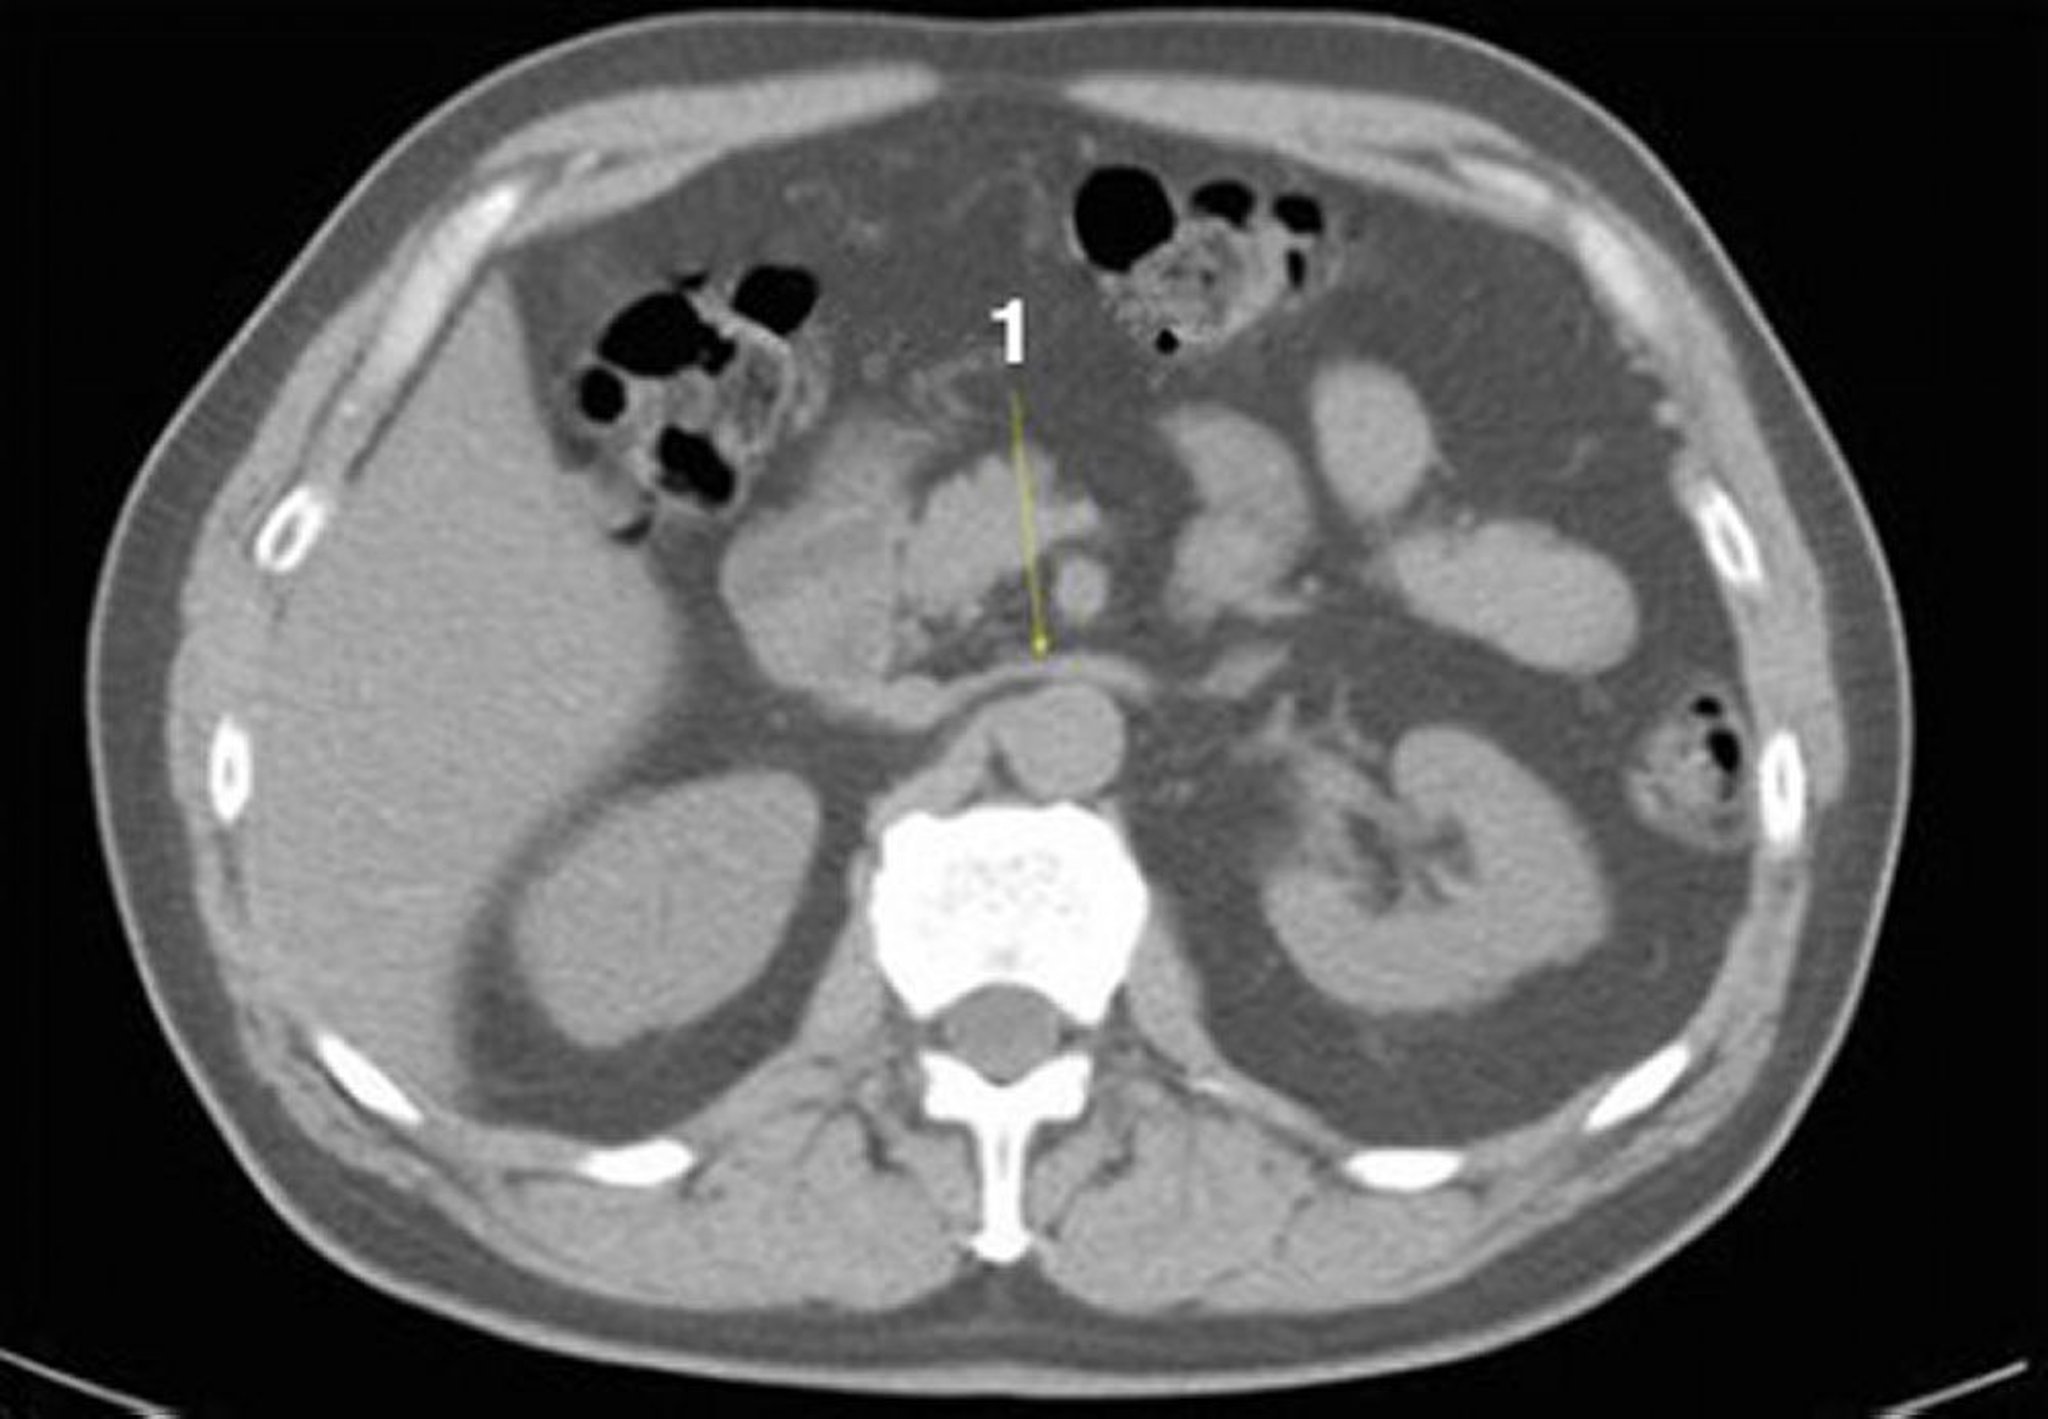

Noncontrast CT Scan of the Abdomen and Pelvis Showing Normal Anatomy (Slide 12)

1 = left renal vein.